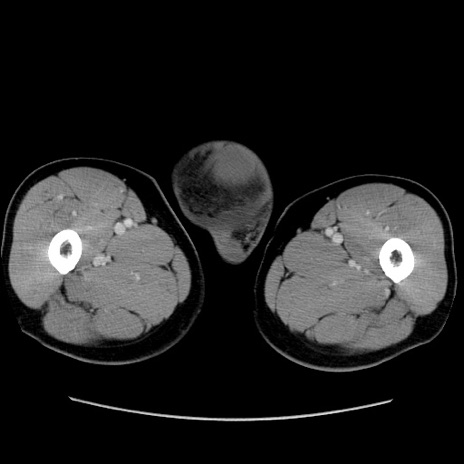

症例34(横断像)

【症例】60歳代 男性

【主訴】右鼠径部膨隆

【現病歴】1年程前より右鼠径部膨隆あり。自己にて還納可能だったため放置していた。3時間前より右鼠径部の脱出を認め、還納困難となり受診。

【既往歴】高血圧

【身体所見】右鼠径部に小児頭大の膨隆あり。弾性硬であり、用手還納は困難。左鼠径部にも膨隆を認める。脱出はなし。